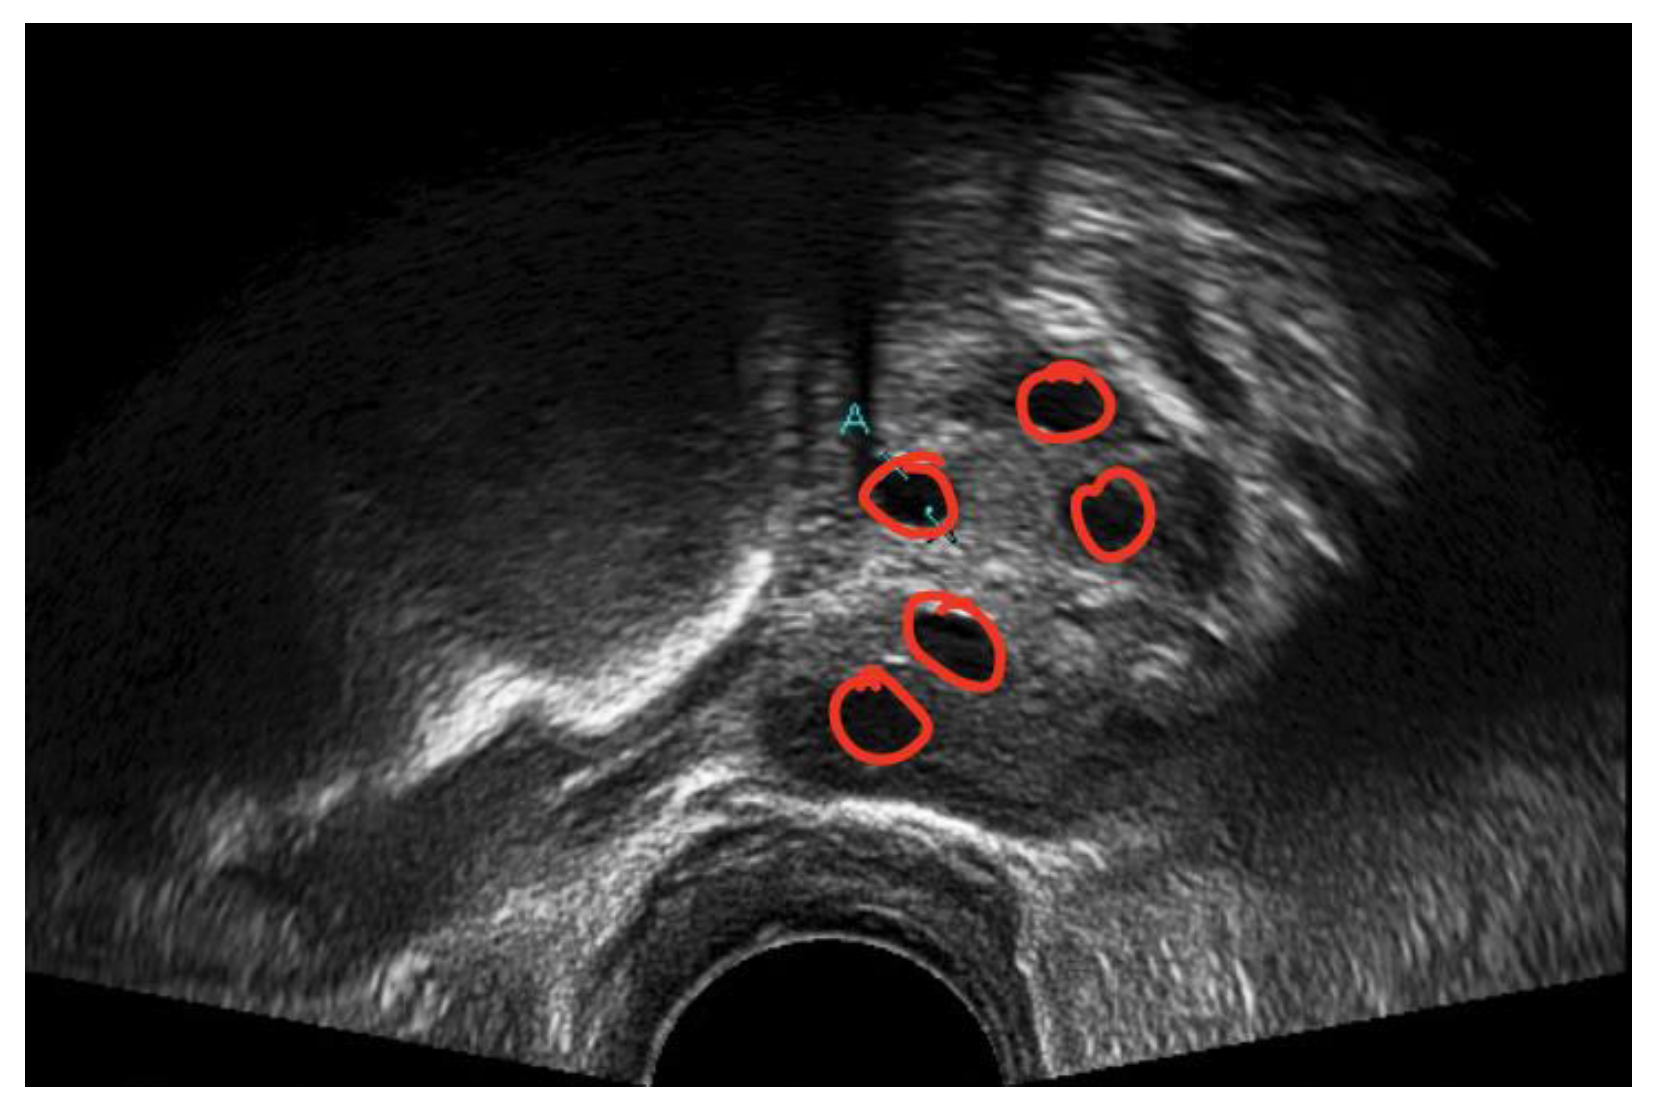

A medical expert was asked to mark the follicle boundary in the ultrasound image to be the ground truth, because this study will be implemented on local ultrasound images. Figure 7 shows the original ultrasound images that were collected by medical experts during patient monitoring, and Figure 8 shows the ultrasound images marked with red circles by medical experts to highlight the existing follicles.

Figure 7.

Original ultrasound acquired from the HCTM MAC unit.

Figure 8.

Image of identified follicles marked by medical expert.